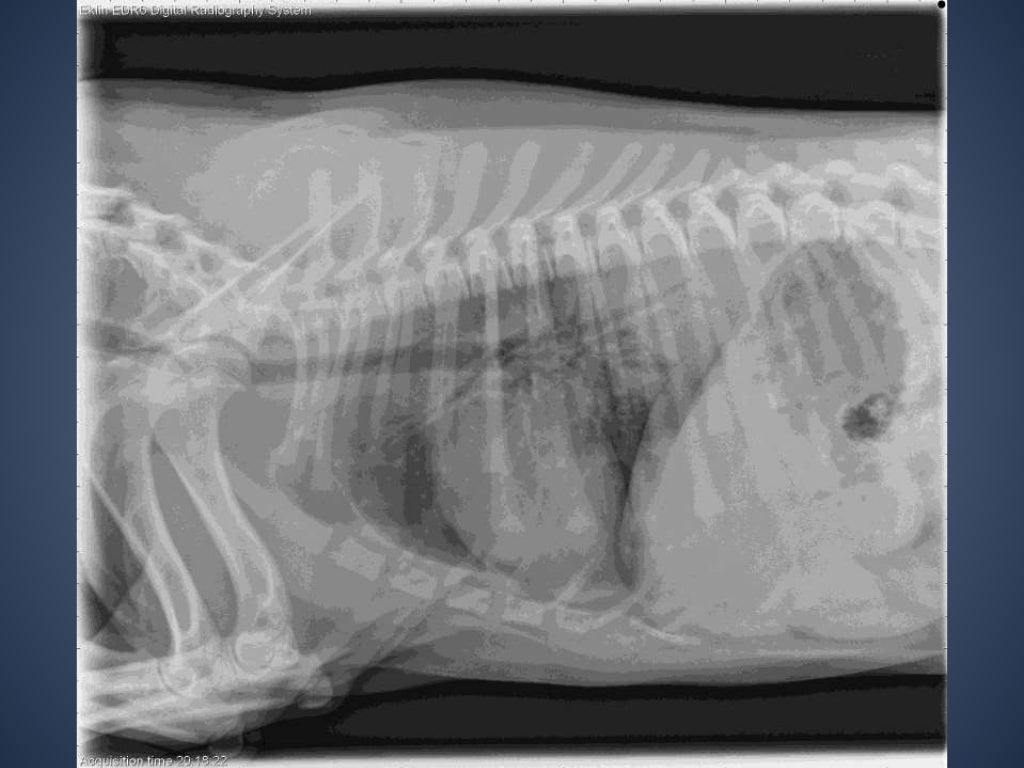

The Radiographic Approach to the Coughing Dog Kennel Cough Xray Thoracic radiographs are recommended for any patient with: Tracheobronchitis is usually suspected whenever a dog demonstrates the distinctive harsh cough and has a history of exposure to other susceptible or affected dogs. In a coughing pet, the recommended screening tests could include a complete blood count, serum biochemistry profile, urinalysis, parasite tests,. The prominent clinical sign of kennel cough is. Kennel Cough Xray.

From www.slideshare.net